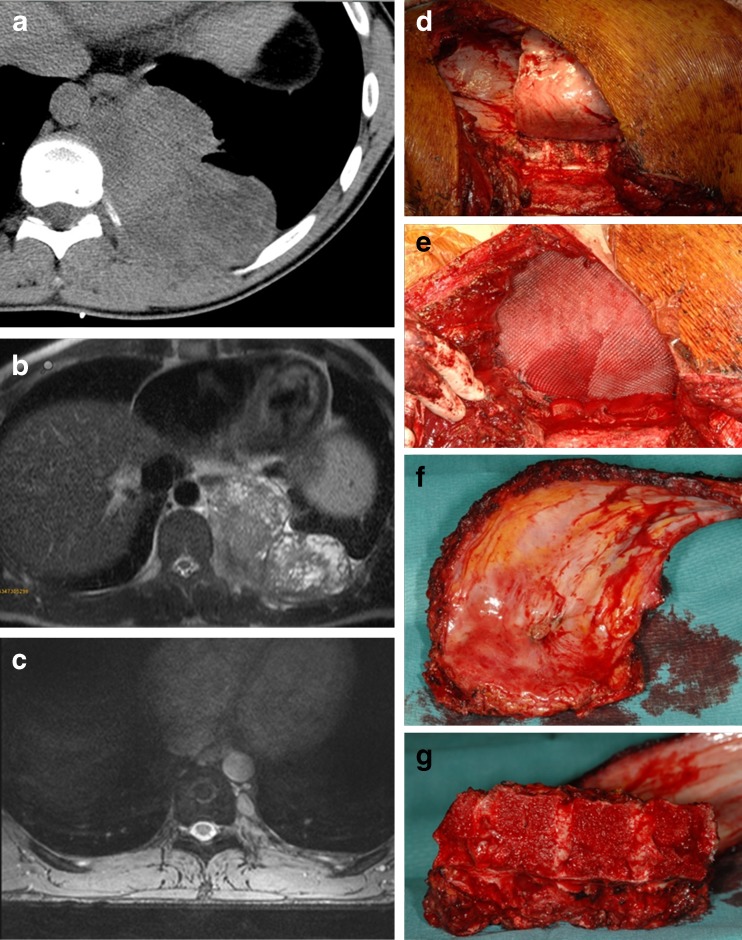

Fig. 1.

a, b CT and MRI of the posterior thoracic wall showing an intrathoracic Ewing’s sarcoma in a 20-year-old male patient. c MRI 8 months following neoadjuvant chemotherapy. d, e Photographs of the intraoperative situs following wide resection of a Ewing’s sarcoma of the posterior thoracic wall and reconstruction using an artificial mesh graft. f, g Photographs of the resected ribs and the thoracic spine following hemicorporectomy